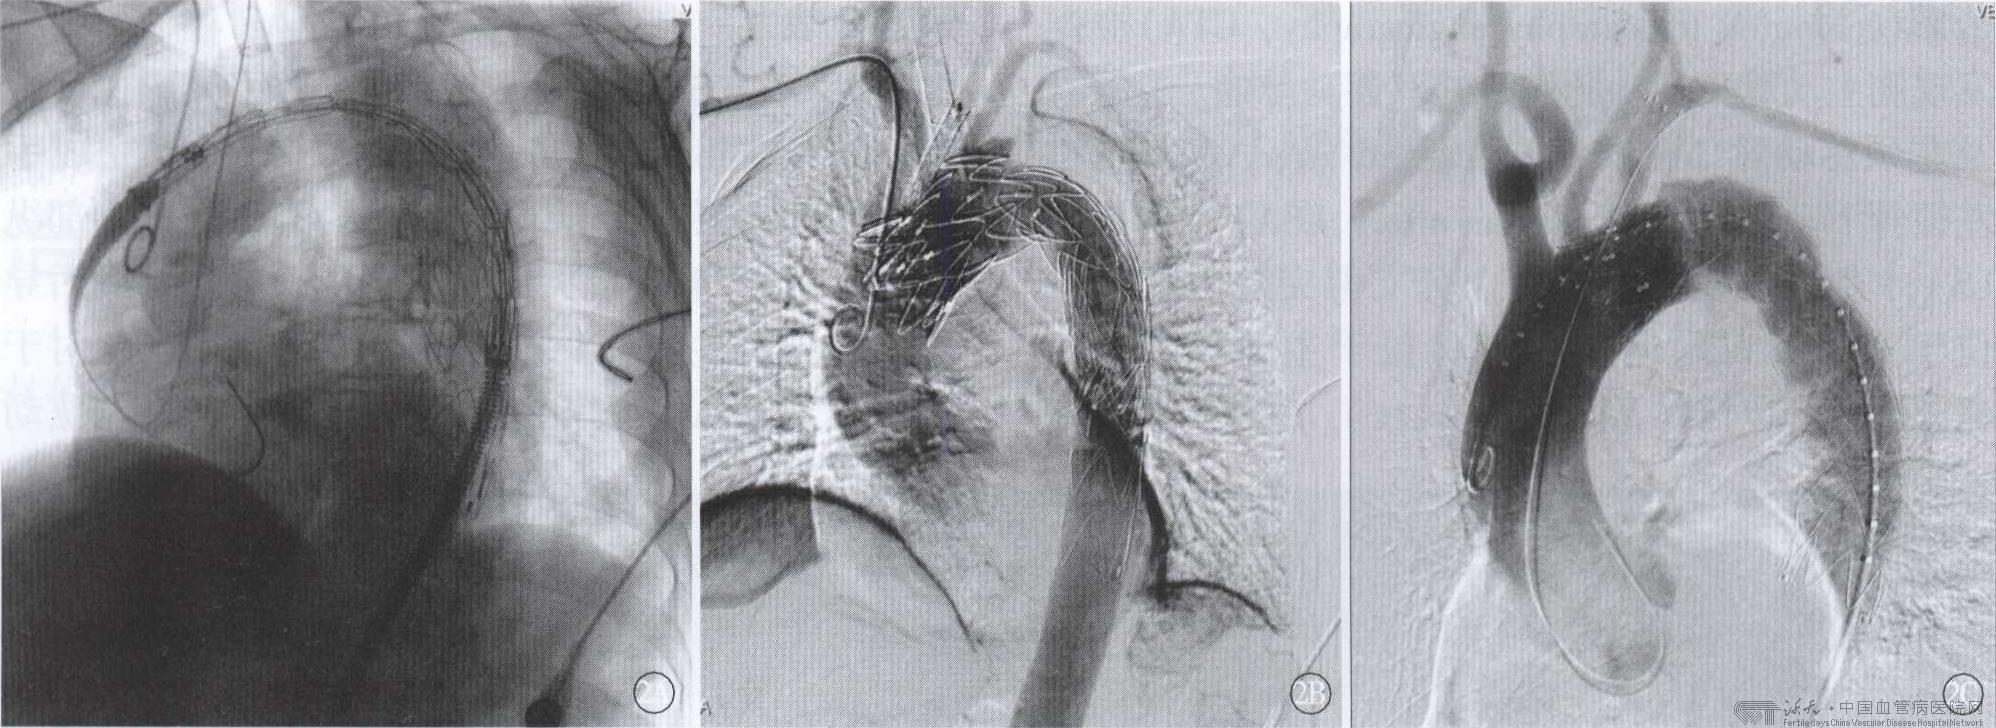

外科开放手术主动脉夹层患者开放手术治疗目前主要用于standford A 型病人,但截瘫发生率可高达5%~40%,其死亡率与内科药物治疗无明显差异。随着人工血管的不断发展,国内孙立忠等首次使用支架“象鼻”术治疗Stanford A 型主动脉夹层,此手术方式的优点是覆盖了夹层内膜破口,扩大真腔,缩小假腔,增加血供。 腔内修复治疗1998 年,Dake 等首先采用腔内修复治疗Standford B 型夹层,此后得到不断发展及改进,从近十年的治疗结果来看,腔内治疗Standford B 型主动脉夹层安全有效,创伤小。

扩展锚定区由于腔内修复术要求近端锚定区应>1.0~1.5mm,对于部分主动脉夹层患者需扩展锚定区,国内外学者为此做了大量研究工作。延长锚定区的治疗进展主要有以下几个方面: Hybrid 技术根据夹层破口发生的位置分别采取不同的杂交技术来延长锚定区。若需覆盖左锁骨下动脉,常见方式为左颈总动脉 ̄左锁骨下动脉旁路;如需覆盖左颈总动脉,常用旁路方式有右颈总动脉 ̄左颈总动脉和右颈总动脉-左颈总动脉 ̄左锁骨下动脉旁路等; 若需覆盖无名动脉此时采用Debranch 技术,此方法需要切开胸骨,但无需体外循环,应用“部分阻断”技术,采用分叉型人工血管,将其近端与升主动脉侧壁吻合, 远端分叉与无名动脉和左颈总动脉吻合,根据术前情况重建或不重建左锁骨下动脉。如果病人不能耐受开胸手术可经左髂动脉到左腋动脉及左颈总动脉、右髂到右腋动脉血管旁路术来延长锚定区。但其远期通畅率不如Debranch 技术。

烟囱技术烟囱技术由Greenberg 于2003 年率先提出,术中操作时首先将裸支架或带膜支架的输送系统预先导入到主动脉分支血管目标位置,接着导入支架型人工血管并完全释放,然后释放预先导入的覆膜支架或者裸支架。这样既可延长锚定区,又可保证分支血管的血流。